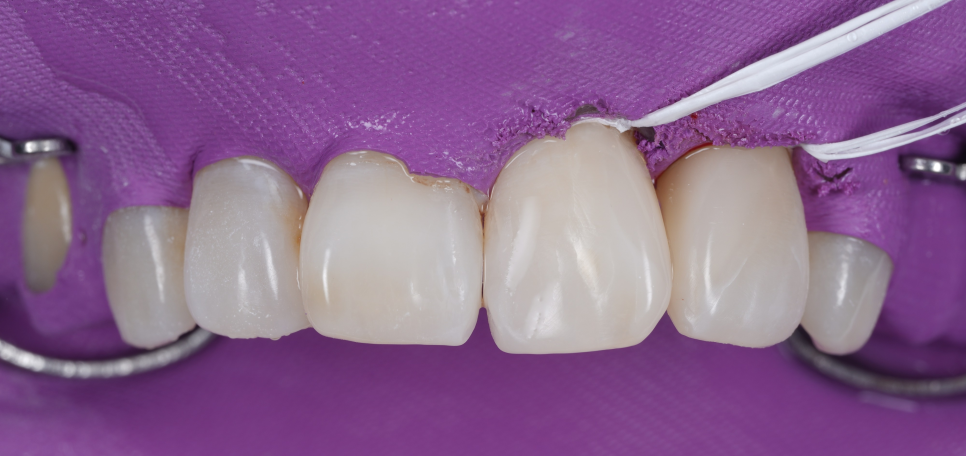

① 우선 잇몸을 짓누르고 있던 기존의 레진 덩어리를 모두 조심스럽게 제거하기로 했습니다.

기존 레진을 제거하려고 혹시 떨어질까 싶어 기구로 살짝 만져봤는데 예상대로 바로 떨어나가졌습니다.

이런 형태가 사실.. 탈락이 굉장히 잘 되거든요^^;

그동안 꽉 막힌 레진 때문에 잇몸이 얼마나 답답하고 불편하셨을지 제 마음도 참 좋지 않았습니다.

잇몸이 숨을 쉬지 못해 질식하고 있는 것과 다름없었으니까요.

불완전한 경계 부분으로 충치도 새로 생겨 큐레이로 계속 확인하면서 충치를 제거해 줬습니다.

그 후 레진 빌드업 단계에 들어갔는데요.

촬영일 : 251230

치아와 레진 사이에 아주 작은 턱이라도 생기지 않도록 매끄럽게 다듬는 데 많은 공을 들였습니다ㅎㅎ

그래야 나중에 환자분이 양치질을 할 때, 치실을 사용할 때 잘 닦여서 세균이 머물 자리가 생기지 않기 때문이죠.